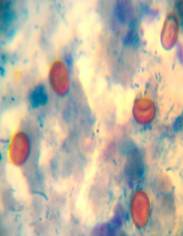

Ооцисти криптоспорідій фарбуються в різні відтінки червоного кольору і мають вигляд округлих утворень діаметром до 5 мкм (Мал.2). Стінки ооцист профарбовуються нерівномірно.

Мал 2. Ооцисти Cryptosporidia spp. Забарвлення за Ціль-Нільсеном. × 1000

Ідентифікацію криіптоспорідій підтверджували за допомогою забарвлення за Цілем-Нільсеном.

Спочатку готували і досліджували під мікроскопом «нативні» препарати  фекалій за  методом Павласека (1990) із застосуванням гліцерину [4]. В краплю фекалій додають кілька крапель гліцерину, при цьому ооцисти криптоспорідій набувають злегка рожевого кольору і стають добре помітними (Мал.1) . Інші найпростіші і частинки не мають властивості змінювати свій колір під впливом гліцерину. Слід зазначити, що таке забарвлення ооцист криптоспорідій може зникнути через 30-40 хв після приготування «нативного»  препарату і тому необхідно досліджувати тільки свіжоприготовані препарати.

Мал 1. Ооцисти Cryptosporidia spp. Нативний препарат з гліцерином. × 400